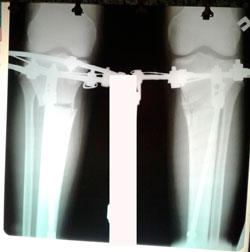

Исходник - 27 лет.

Дата операции - 07.08.2020

image-07-08-20-10-23-1.jpg

image-07-08-20-10-23-5.jpg